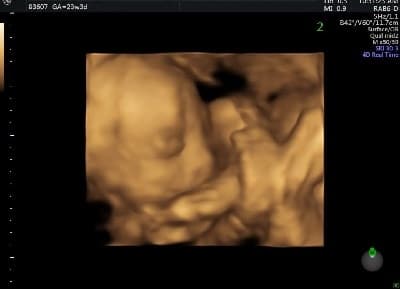

Ultrasound Photos at 23 Weeks Pregnant With Twins